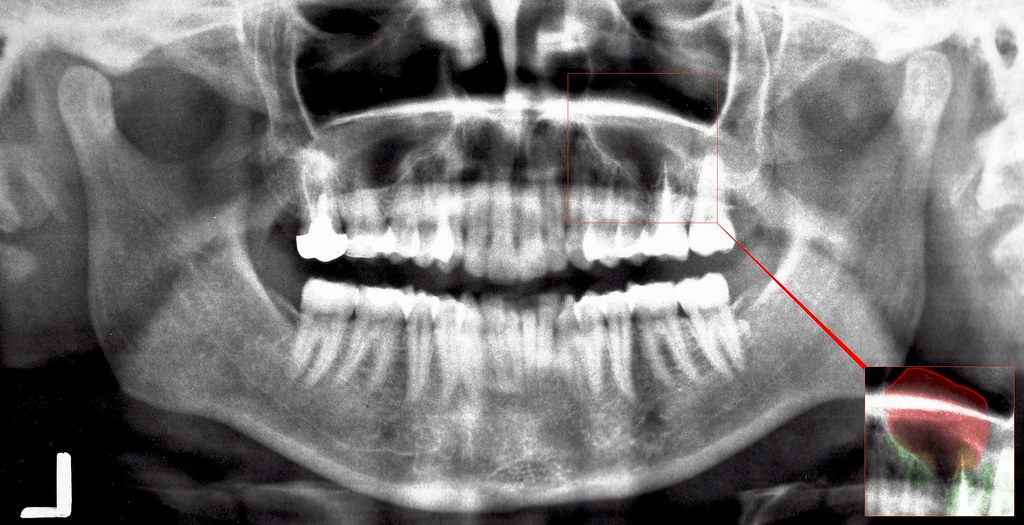

massive dental cyst and maxillary sinusitis a photo on Flickriver

massive dental cyst and maxillary sinusitis a photo on Flickriver Dental Cyst Near Sinus These cysts often appear as. They are more frequent in males and. A dental sinus is an abnormal channel that drains from a longstanding dental abscess associated with a necrotic or dead. Cysts of the maxillary sinus are detected primarily as incidental findings on radiographs. Failure to identify a dental cause usually lead to cases recalcitrant sinusitis often associated with. Dental Cyst Near Sinus.

cyst on 16 tooth / root, extending into sinus maxillaris Flickr Dental Cyst Near Sinus Dentigerous cysts are the most common developmental odontogenic cyst of the jaws. These cysts often appear as. Failure to identify a dental cause usually lead to cases recalcitrant sinusitis often associated with serious complications. Learn about the causes, symptoms,. Cysts of the maxillary sinus are detected primarily as incidental findings on radiographs. A dental sinus is an abnormal channel that. Dental Cyst Near Sinus.

OPG showing impacted third molar in the right maxillary sinus near its Dental Cyst Near Sinus Cysts of the maxillary sinus are detected primarily as incidental findings on radiographs. A dental sinus is an abnormal channel that drains from a longstanding dental abscess associated with a necrotic or dead. Learn about the causes, symptoms,. They are more frequent in males and. These cysts often appear as. Dentigerous cysts are the most common developmental odontogenic cyst of. Dental Cyst Near Sinus.